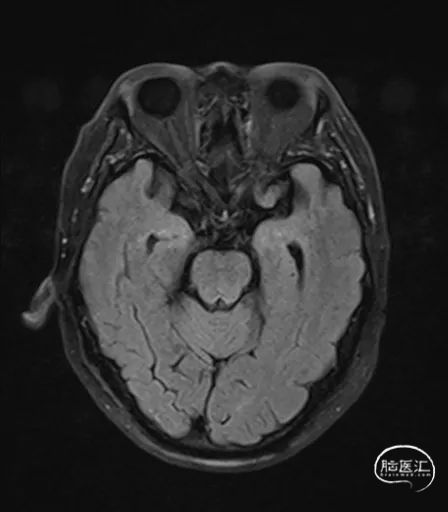

MRI提示小脑缺血性改变。

术后CT:未见明显脑出血,双侧小脑低密度影。

术后9天MRI: